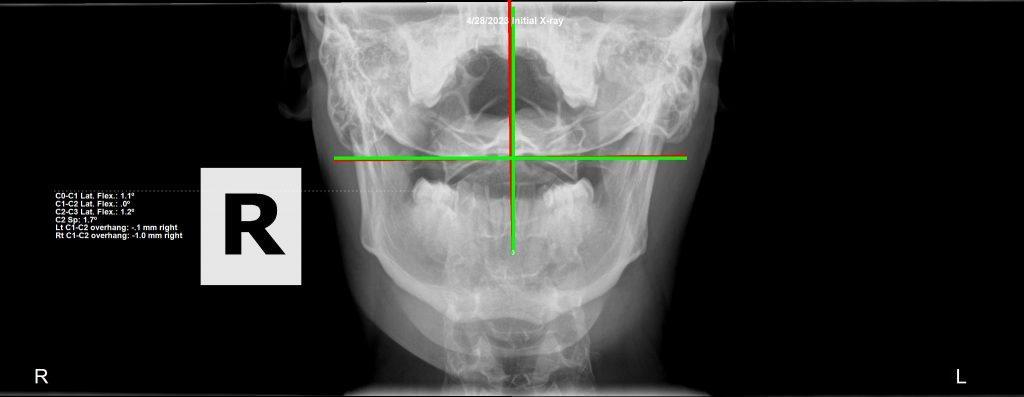

Initial cervical X-ray — subluxation analysis Royal Palm Beach

Initial Presentation